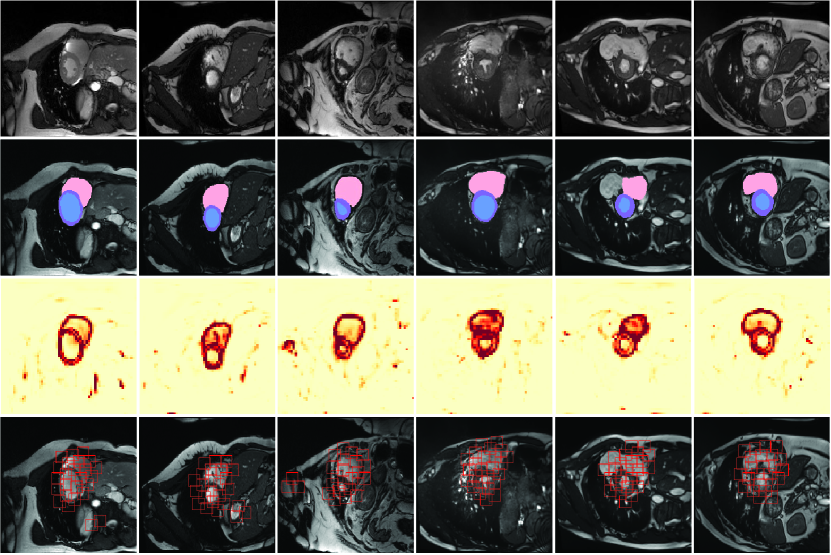

Refer to caption

Figure 7: Visualization of boundary-around windows generation by BLT on the ISIC 2018 dataset. From top to bottom: the raw images, the ground truth, the entropy maps, and the generated boundary-aware windows. In entropy maps, the darker the color, the higher the entropy.

Figure 8: Visualization of boundary-around windows generation by BLT on the ACDC datasets. From top to bottom: the raw images, the ground truth, the entropy maps, and the generated boundary-aware windows. In entropy maps, the darker the color, the higher the entropy.

To better evaluate the effectiveness of BLT, we further plot the generated entropy maps and boundary-around windows as shown in Figs. 7 and 8. In general, boundaries are effectively localized through entropy calculation, based on which BLT can build boundary-specific mid-range dependency for performance improvement.